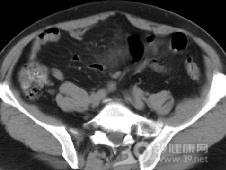

2.B超及CT检查:B超及CT检查可区别在腹膜后还是腹腔内,囊肿、囊实性、实体瘤,并可看出肿块大小、边界情况、囊性者可看出囊内有无分隔。